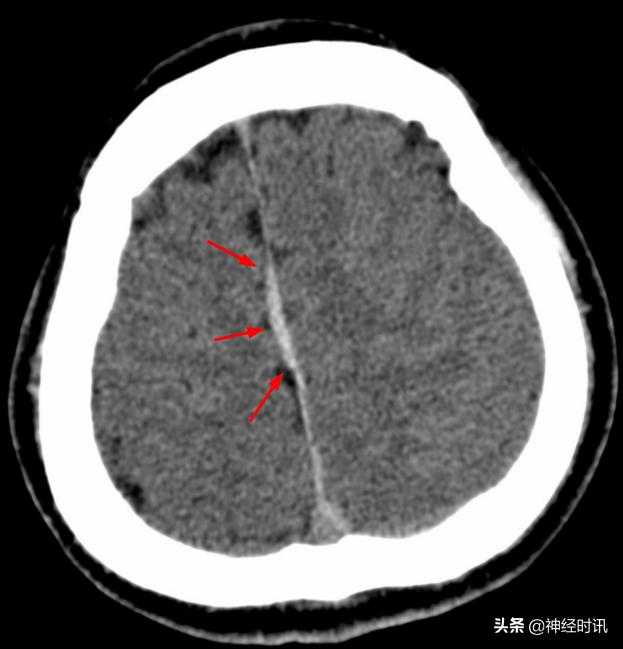

典型的大脑镰前部少量蛛血,血肿的边缘毛糙(红箭)且抵达胼胝体膝部的前缘(黄箭头)。4天后复查头颅CT平扫,相应部位少量蛛血基本吸收。

另一例表现类似的大脑镰前部少量蛛血,血肿的边缘总是有一种毛毛糙糙的感觉(红箭)。

大脑镰前下部极少量蛛血(红箭),淡黄色虚线框勾勒出胼胝体膝部,血肿的边缘仍然是 模模糊糊的,注意这幅图中双侧大脑半球见多发斑点状高密度影(绿箭头),随访证实系伪影所致,而非弥漫性轴索损伤。夜班急诊时CT诊断的难点在于其密度分辨率有限(相较于MR),5mm层厚带来的容积效应干扰,有时候再加上噪声形成的伪影,就非常考验平时的基本功以及经验积累了。

红箭所指的大脑镰局部呈连续的长条状高密度影,容易被误诊为少量蛛血,此系大脑镰局部不完全钙化所致。注意观察密度增高的大脑镰边缘非常光滑、且居中(红箭),与少量蛛血形成的偏密征、边缘毛糙等征象恰好相反。

间断性的大脑镰不完全线状钙化(红箭),同样呈边缘光滑、居中改变。

国内一些文献将大脑镰一侧不对称的高密度影被定义为“偏密征”,并认为上述影像学特征是诊断大脑镰旁少量蛛网膜下腔出血的可靠征象,可提示出血部位位于“偏密征”附近,或继发于邻近的其它颅内损伤。

本例颅脑外伤患者的大脑镰右旁可见“偏密征”,但这个血肿的边缘非常光滑(红箭)且未延伸至邻近脑沟内,边缘似乎还带有一些张力感,笔者觉得此例诊断为大脑镰旁硬膜下血肿更合适。但不管怎么说,“偏密征”用于鉴别是否存在局限性的脑外伤还是很有用的。